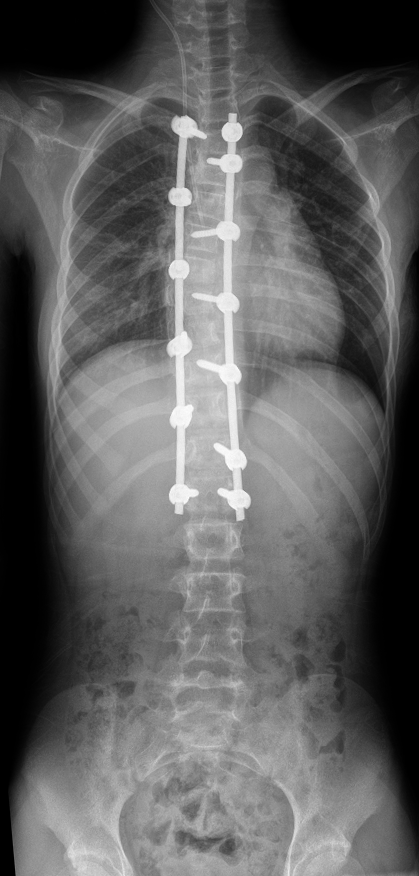

全自动全景成像(选配)

三次点击,两个步骤,一气呵成

全过程一分钟内完成,摄影条件智能设定,根据不同体厚智能曝光补偿,宽幅窄缝按需选择,无需往返机房调整机架位置,一气呵成自动全景成像